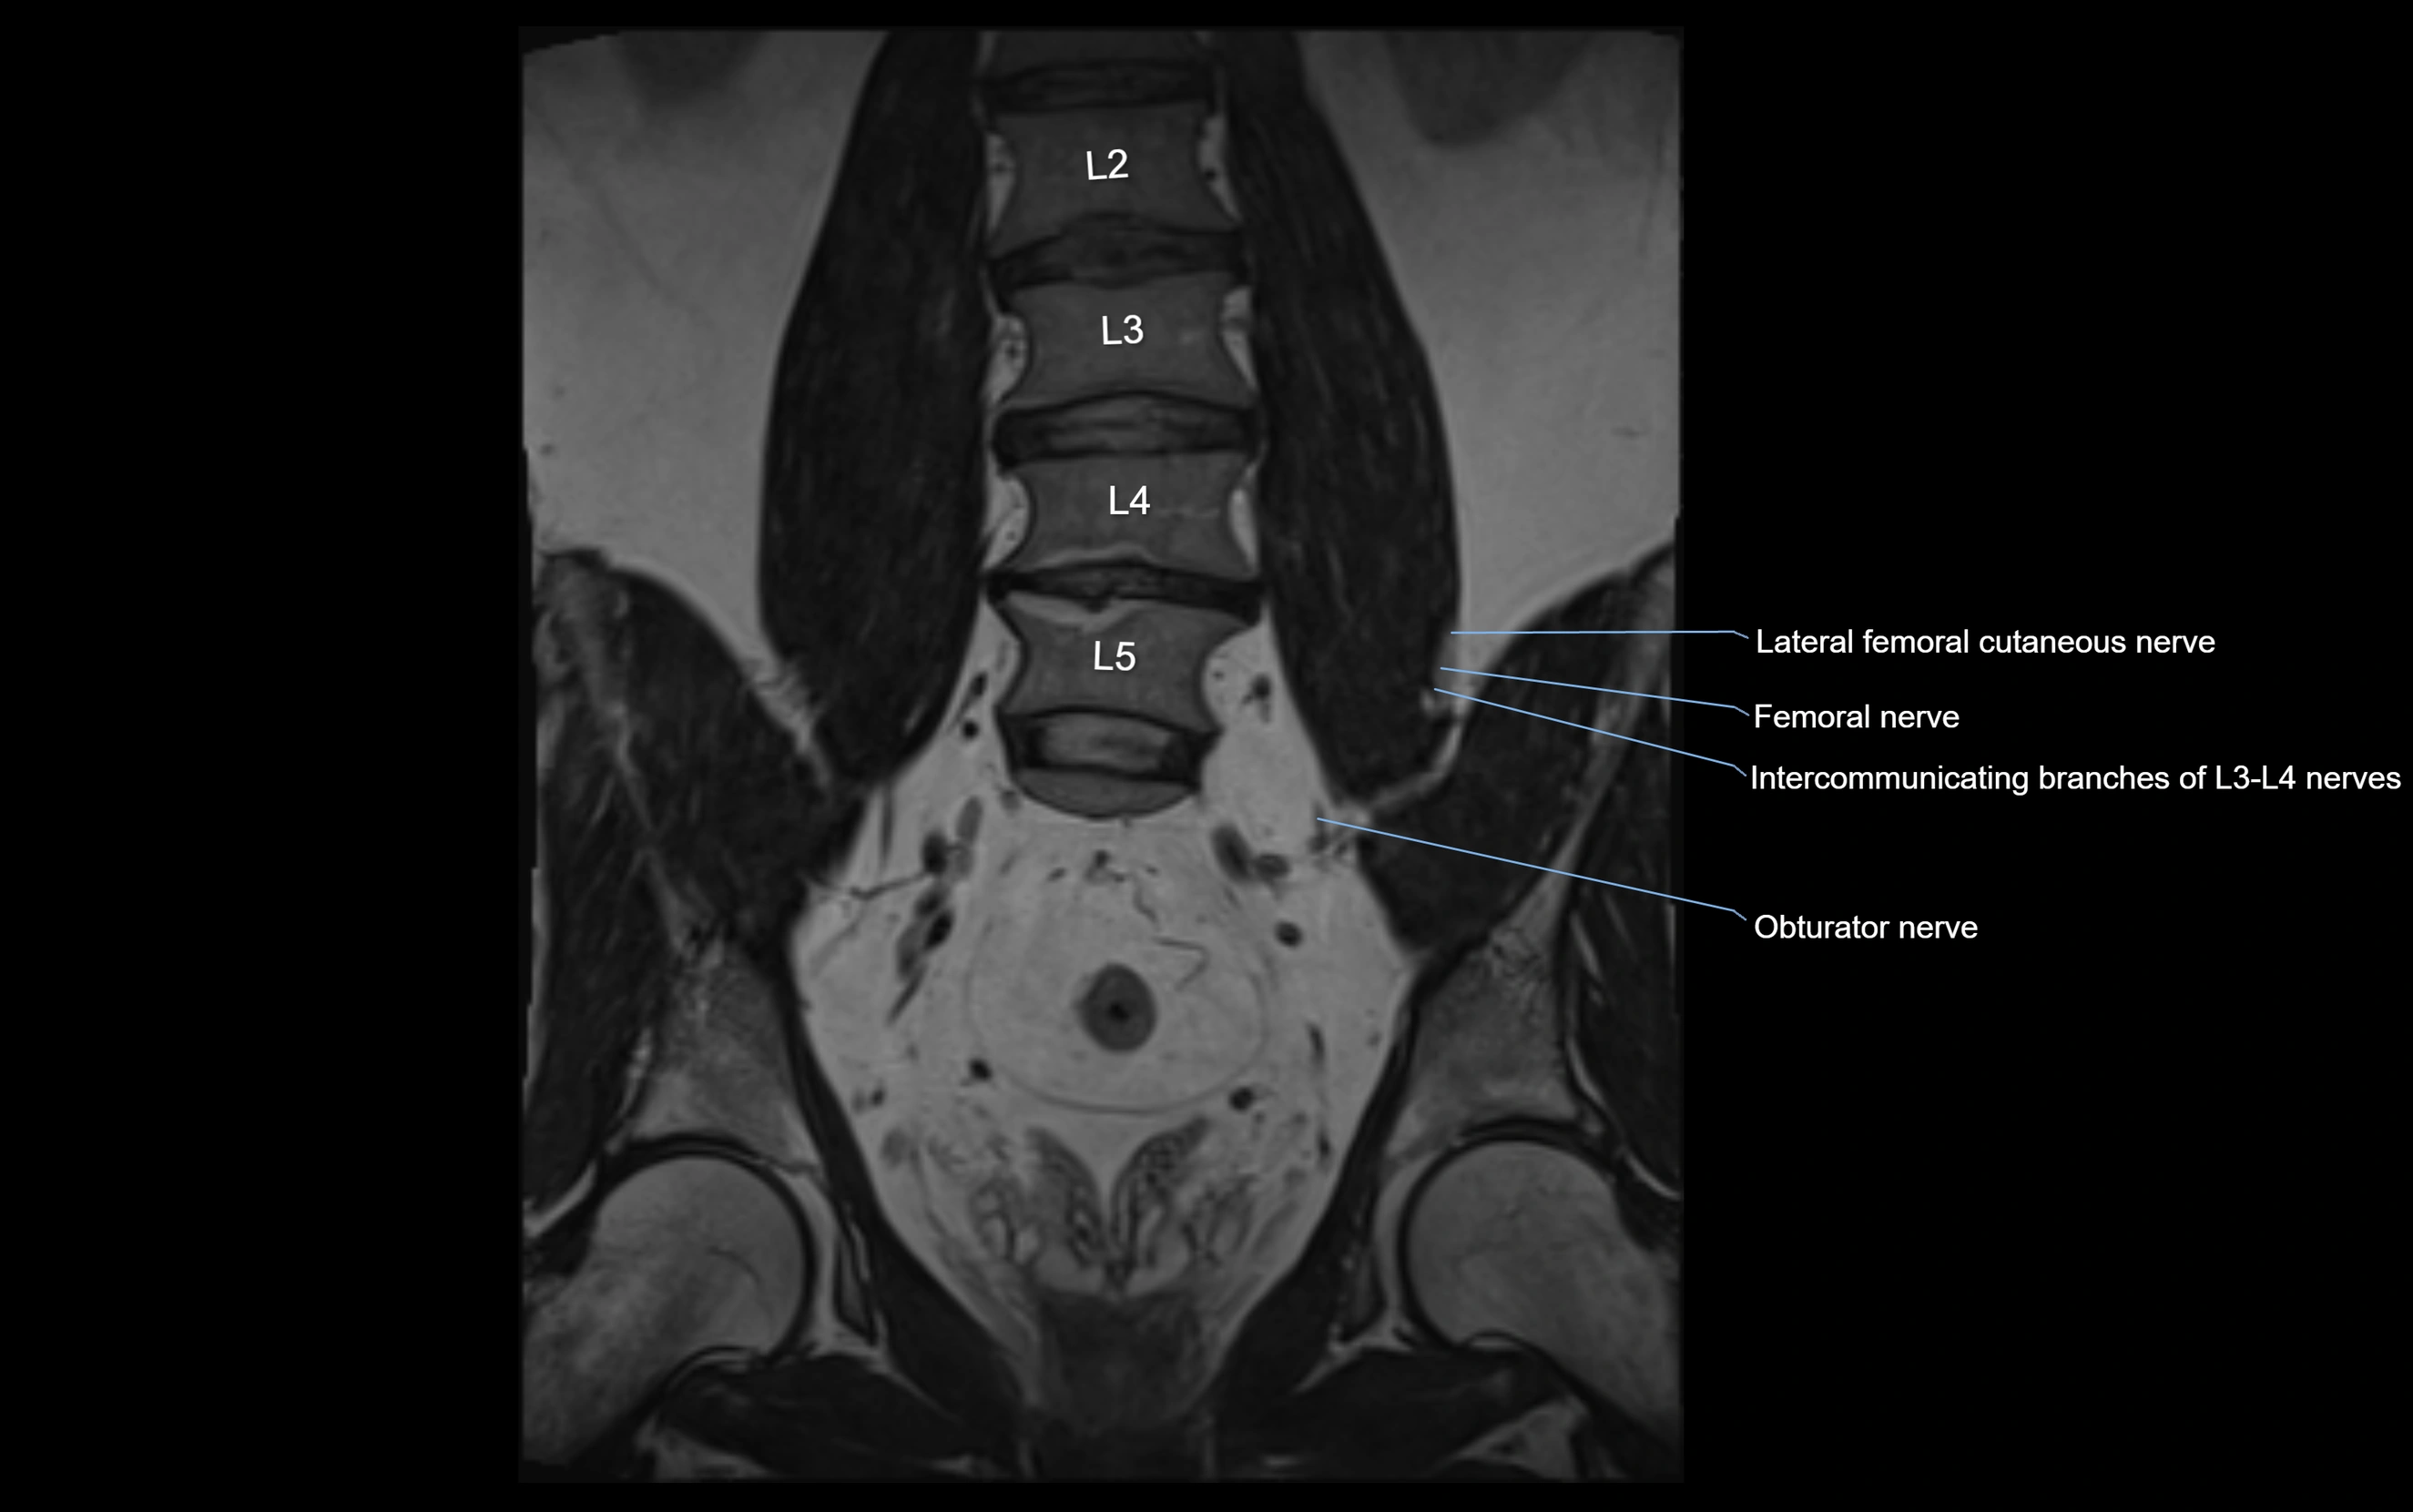

MRI Appearance

T1-weighted images:

• Nerve appears as a very thin low-to-intermediate signal intensity structure

• Surrounded by bright fat, aiding visualization

T2-weighted images:

• Nerve shows intermediate to mildly hyperintense signal compared to muscle

• Pathological involvement appears brighter

STIR (Short Tau Inversion Recovery):

• Normal nerve appears dark

• Inflamed or entrapped nerve appears bright hyperintense

T1 Fat-Sat Post-Contrast:

• Normal nerve enhances minimally

• Pathologic nerve (neuritis, entrapment, tumor infiltration) shows focal or diffuse enhancement

3D T2 SPACE / CISS:

• Nerve appears intermediate to mildly hyperintense compared to muscle

• Surrounded by bright fat or CSF, improving visualization

• Best sequence for mapping small pelvic nerves such as the anococcygeal